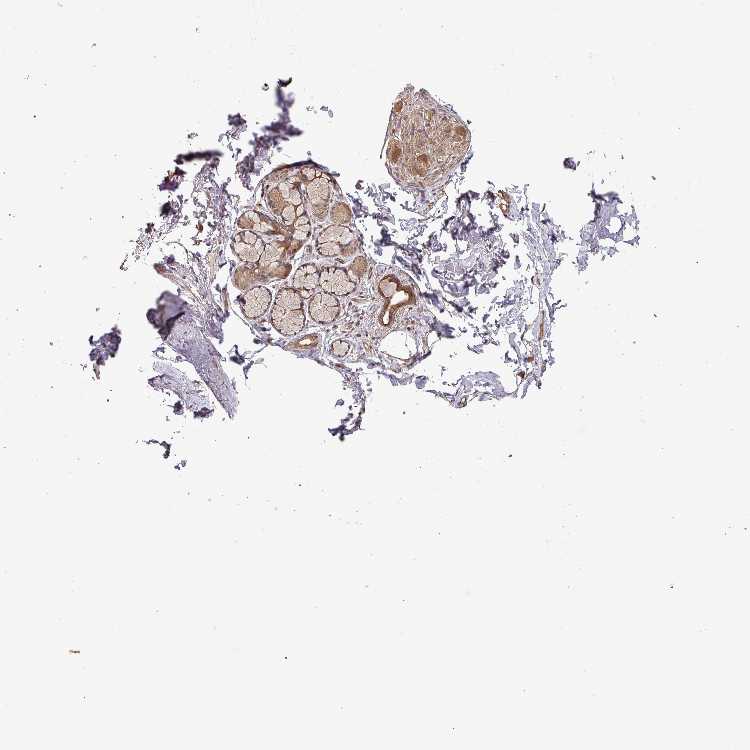

SOFT TISSUE 1 - Antibody stainingi

Antibody staining in the annotated cell types in the current human tissue is reported as not detected, low, medium, or high, based on conventional immunohistochemistry profiling in selected tissues. This score is based on the combination of the staining intensity and fraction of stained cells.

Each image is clickable and will lead to virtual microscopy that enables deeper exploration of all samples and also displays staining intensity scores, fraction scores and subcellular localization as well as patient and tissue information for each sample.

Antibody HPA045817

Fibroblasts Medium

Peripheral nerve Medium

SOFT TISSUE 2 - Antibody stainingi

Peripheral nerve Low